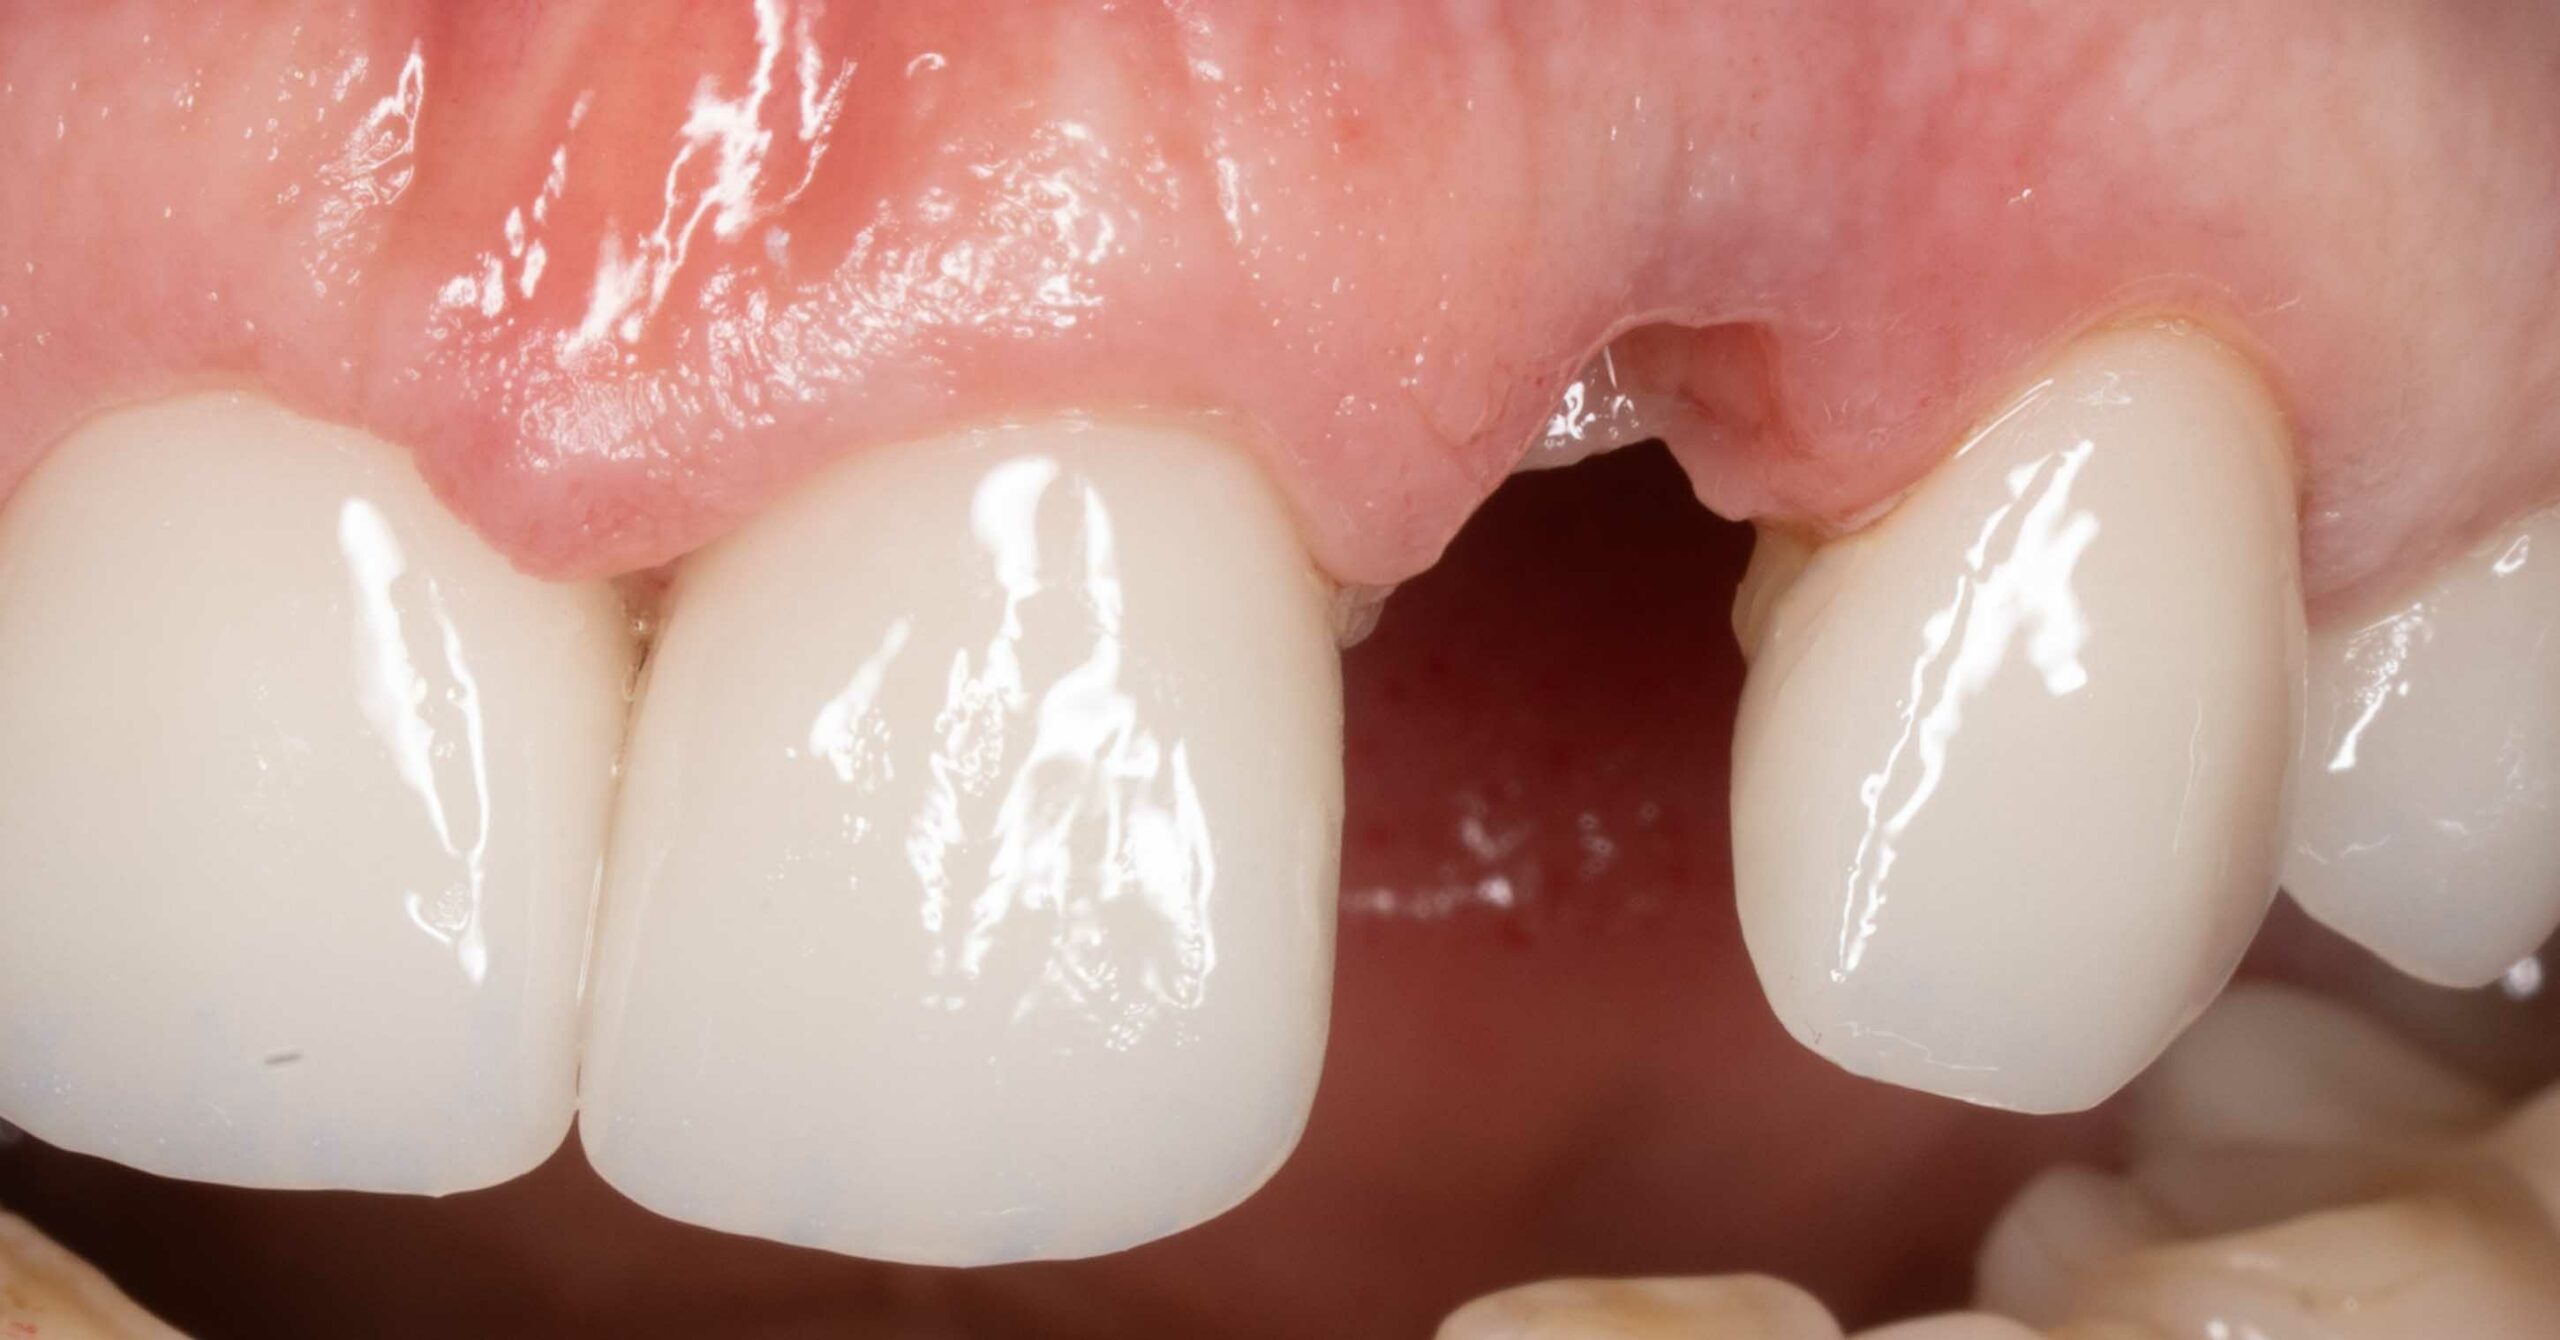

Odbudowa braku oraz korekta estetyki

Pacjentka zgłosiła się z powodu utraty siekacza bocznego prawego.

Leczenie obejmowało:

- wprowadzenie implantu w pozycji 12

- chirurgiczną plastykę dziąsła

- pełnoceramiczne korony na implancie oraz licówki na siekaczach środkowych

Leczenie przeprowadził lek. dent. Kamil Kikowicz